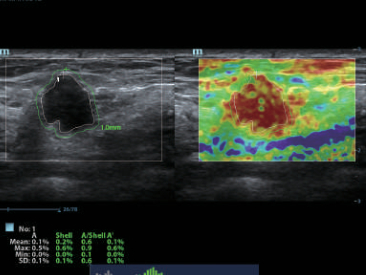

–€–Ψ–Ϋ–Ψ–Κ―Ä–Η―¹―²–Α–Μ–Μ–Η―΅–Β―¹–Κ–Η–Β –¥–Α―²―΅–Η–Κ–Η ―¹ ―²–Β―Ö–Ϋ–Ψ–Μ–Ψ–≥–Η–Β–Ι 3–Δ?

–ë–Μ–Α–≥–Ψ–¥–Α―Ä―è ―¹–Ψ―΅–Β―²–Α–Ϋ–Η―é ―²–Β―Ö–Ϋ–Ψ–Μ–Ψ–≥–Η–Η 3–Δ? (–Δ―Ä–Ψ–Ι–Ϋ–Ψ–Ι ―¹–Ψ–≥–Μ–Α―¹―É―é―â–Η–Ι ―¹–Μ–Ψ–Ι, ―²–Β―Ö–Ϋ–Ψ–Μ–Ψ–≥–Η―è –Ω–Ψ–Μ–Ϋ–Ψ―¹―²―¨―é ―Ä–Α–Ζ–¥–Β–Μ–Β–Ϋ–Ϋ―΄―Ö –Κ―Ä–Η―¹―²–Α–Μ–Μ–Ψ–≤, ―²–Β―Ä–Φ–Ψ–Κ–Ψ–Ϋ―²―Ä–Ψ–Μ―¨ –Α–Κ―É―¹―²–Η―΅–Β―¹–Κ–Ψ–Ι –Μ–Η–Ϋ–Ζ―΄) –Η –Φ–Ψ–Ϋ–Ψ–Κ―Ä–Η―¹―²–Α–Μ–Μ–Η―΅–Β―¹–Κ–Η―Ö –¥–Α―²―΅–Η–Κ–Ψ–≤ –Ψ–±–Β―¹–Ω–Β―΅–Η–≤–Α–Β―²―¹―è –Κ–Α–Κ –±–Ψ–Μ–Β–Β –≤―΄―¹–Ψ–Κ–Α―è ―Ä–Α–Ζ―Ä–Β―à–Α―é―â–Α―è, ―²–Α–Κ –Η –Ω―Ä–Ψ–Ϋ–Η–Κ–Α―é―â–Α―è ―¹–Ω–Ψ―¹–Ψ–±–Ϋ–Ψ―¹―²―¨, –≤ ―Ä–Β–Ζ―É–Μ―¨―²–Α―²–Β ―΅–Β–≥–Ψ ―Ä–Β―à–Α–Β―²―¹―è –Ω―Ä–Ψ–±–Μ–Β–Φ–Α –Η―¹―¹–Μ–Β–¥–Ψ–≤–Α–Ϋ–Η–Ι ―²–Β―Ö–Ϋ–Η―΅–Β―¹–Κ–Η ―¹–Μ–Ψ–Ε–Ϋ―΄―Ö –Ω–Α―Ü–Η–Β–Ϋ―²–Ψ–≤.